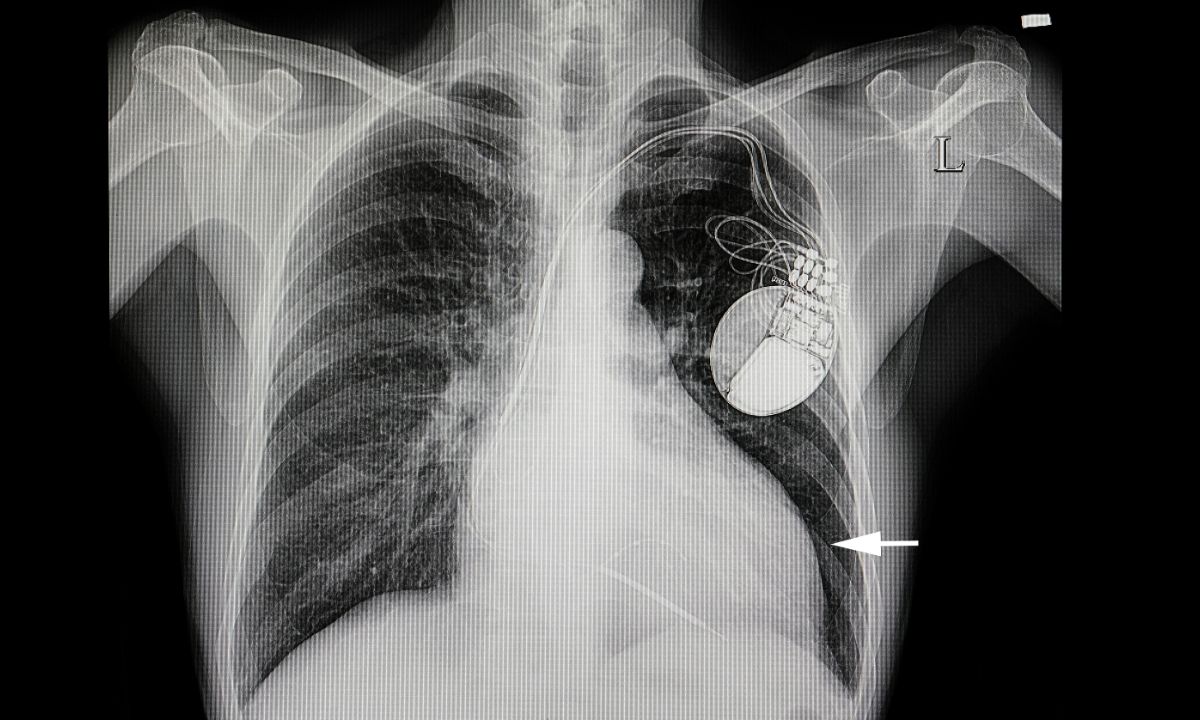

Οι γιατροί χρησιμοποιούν τον όρο πνευμονικό οίδημα για να περιγράψουν τη διαδικασία συσσώρευσης υγρού στον πνεύμονα. Το πνευμονικό οίδημα οφείλεται στην πλειονότητα των περιπτώσεων σε καρδιαγγειακή επιπλοκή (καρδιογενές ή καρδιογενητικό πνευμονικό οίδημα).

Το καρδιογενές πνευμονικό οίδημα είναι αποτέλεσμα της αυξημένης πίεσης και καταπόνησης της καρδιάς.